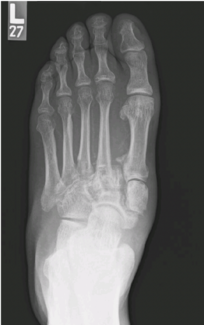

But, we had a custom 3D implant made. I resected the non-union site and put the implant in and fused his ankle and he's done well. And I've done the same thing for non-union of the fibula as well. Also, we've been using him for brachymetatarsia in the past. I've used both allogenic bone and autogenous bone, and I've seen both of them at times resorb. I've used distraction techniques. Maybe it's, it's worked here and there, but not consistently in my hands. But this, uh, metallic 3D printed implant, uh, lengthens the metatarsal, it does not collapse, and it's done very well.